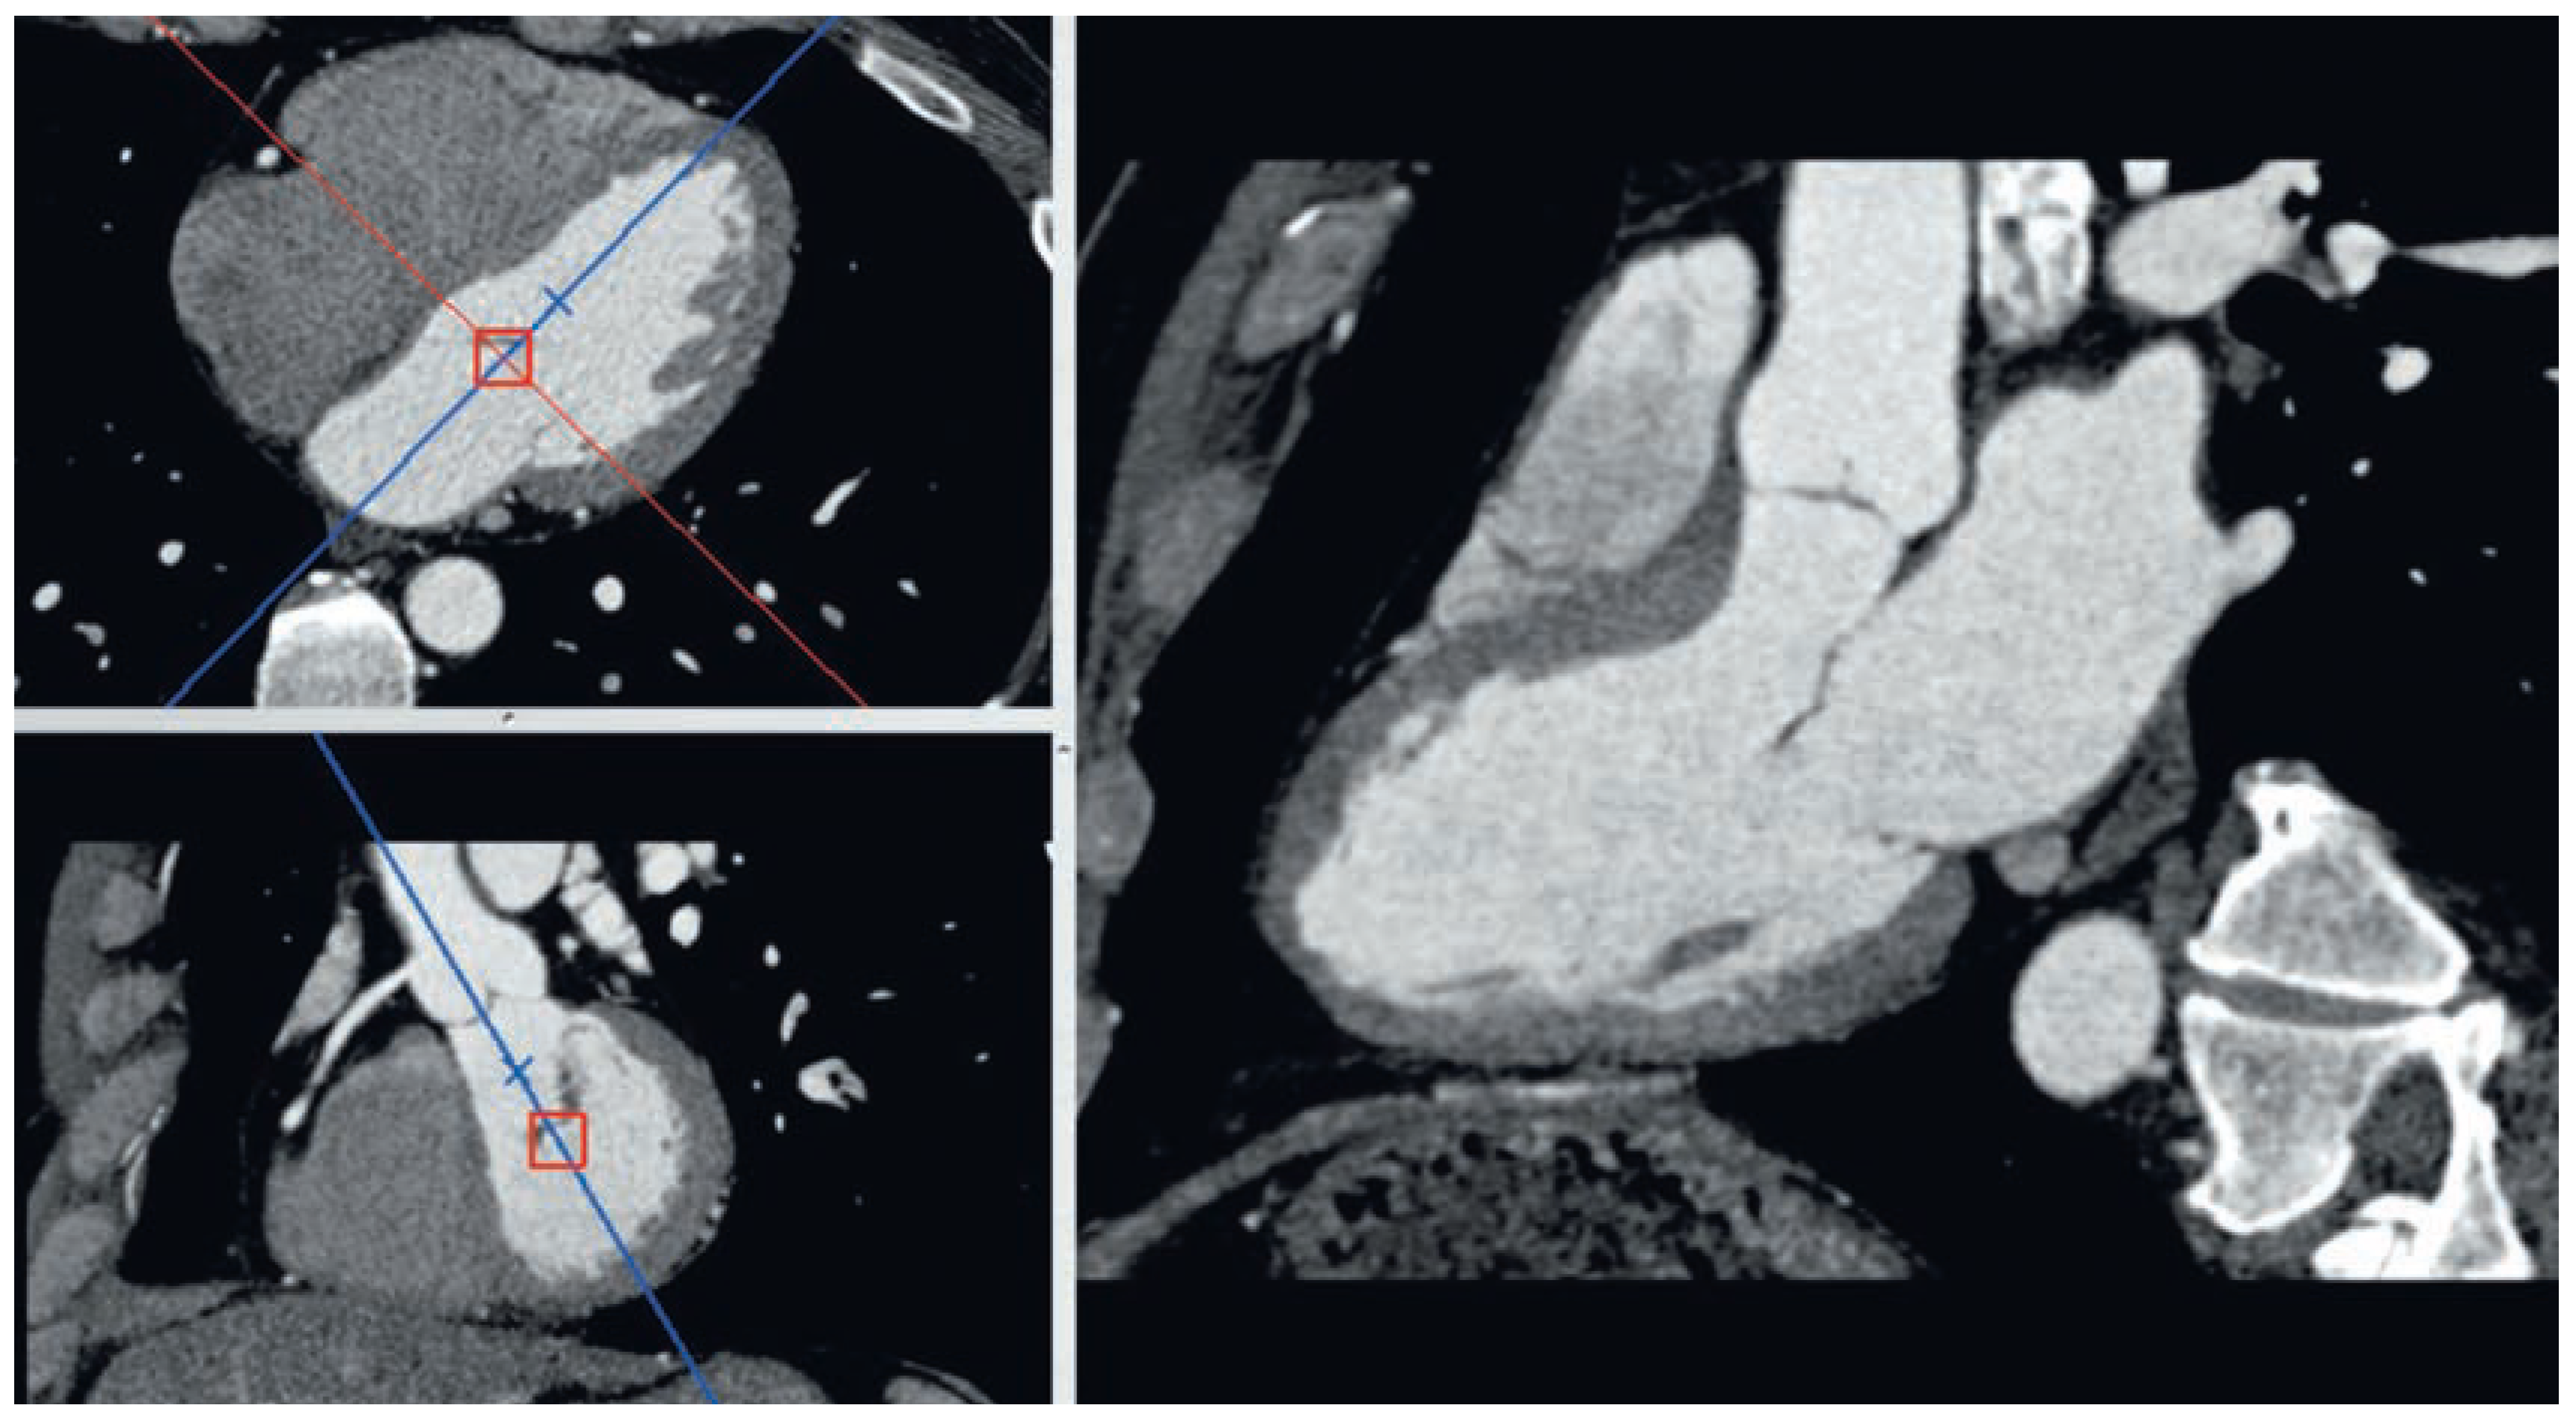

All coronary CTA studies are acquired in ECG-gated dynamic mode where different image sets are obtained at different times in the cardiac cycle. While individual time windows of end-systolic and end-diastolic phases are usually used for adequate visualisation of the coronary arteries at times where they present minimal velocity, it is also possible to reconstruct the data for all phases of the cardiac cycle from the same original dataset. It is thereby possible to generate dynamic cine sequences of the whole heart and to select oblique reformatted planes along standard anatomical axis of the heart (

Figure 4). These reconstructed data provide high quality images for the assessment of heart anatomy and ventricular function. Ventricular volumes and ejection fraction as well as regional wall motion and wall thickening parameters can be measured quantitatively with high degree of accuracy due to the high spatial resolution of the images [

12,

13,

14].